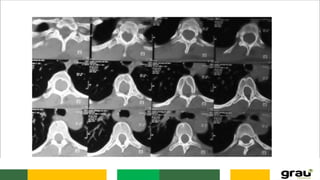

VÉRTEBRAS

CORPO

CANAL MEDULAR (FORAME

VERTEBRAL)

FACETA ARTICULAR

PROCESSOS TRANSVERSOS

PROCESSO ESPINHOSO

VÉRTEBRAS CORPO CANAL MEDULAR (FORAME VERTEBRAL) FACETAARTICULAR PROCESSOS TRANSVERSOS PROCESSO ESPINHOSO